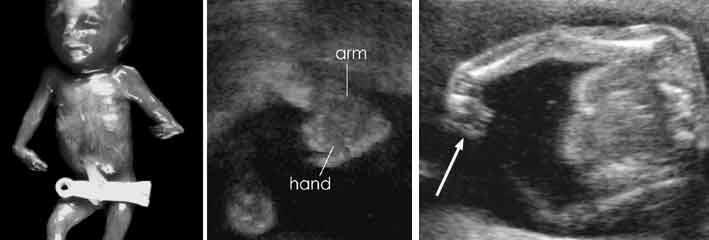

Phocomelia

Phocomelia

Phocomelia

What is Phocomelia?

Absence of middle segment

foot and hand would be attached to femur and humerus